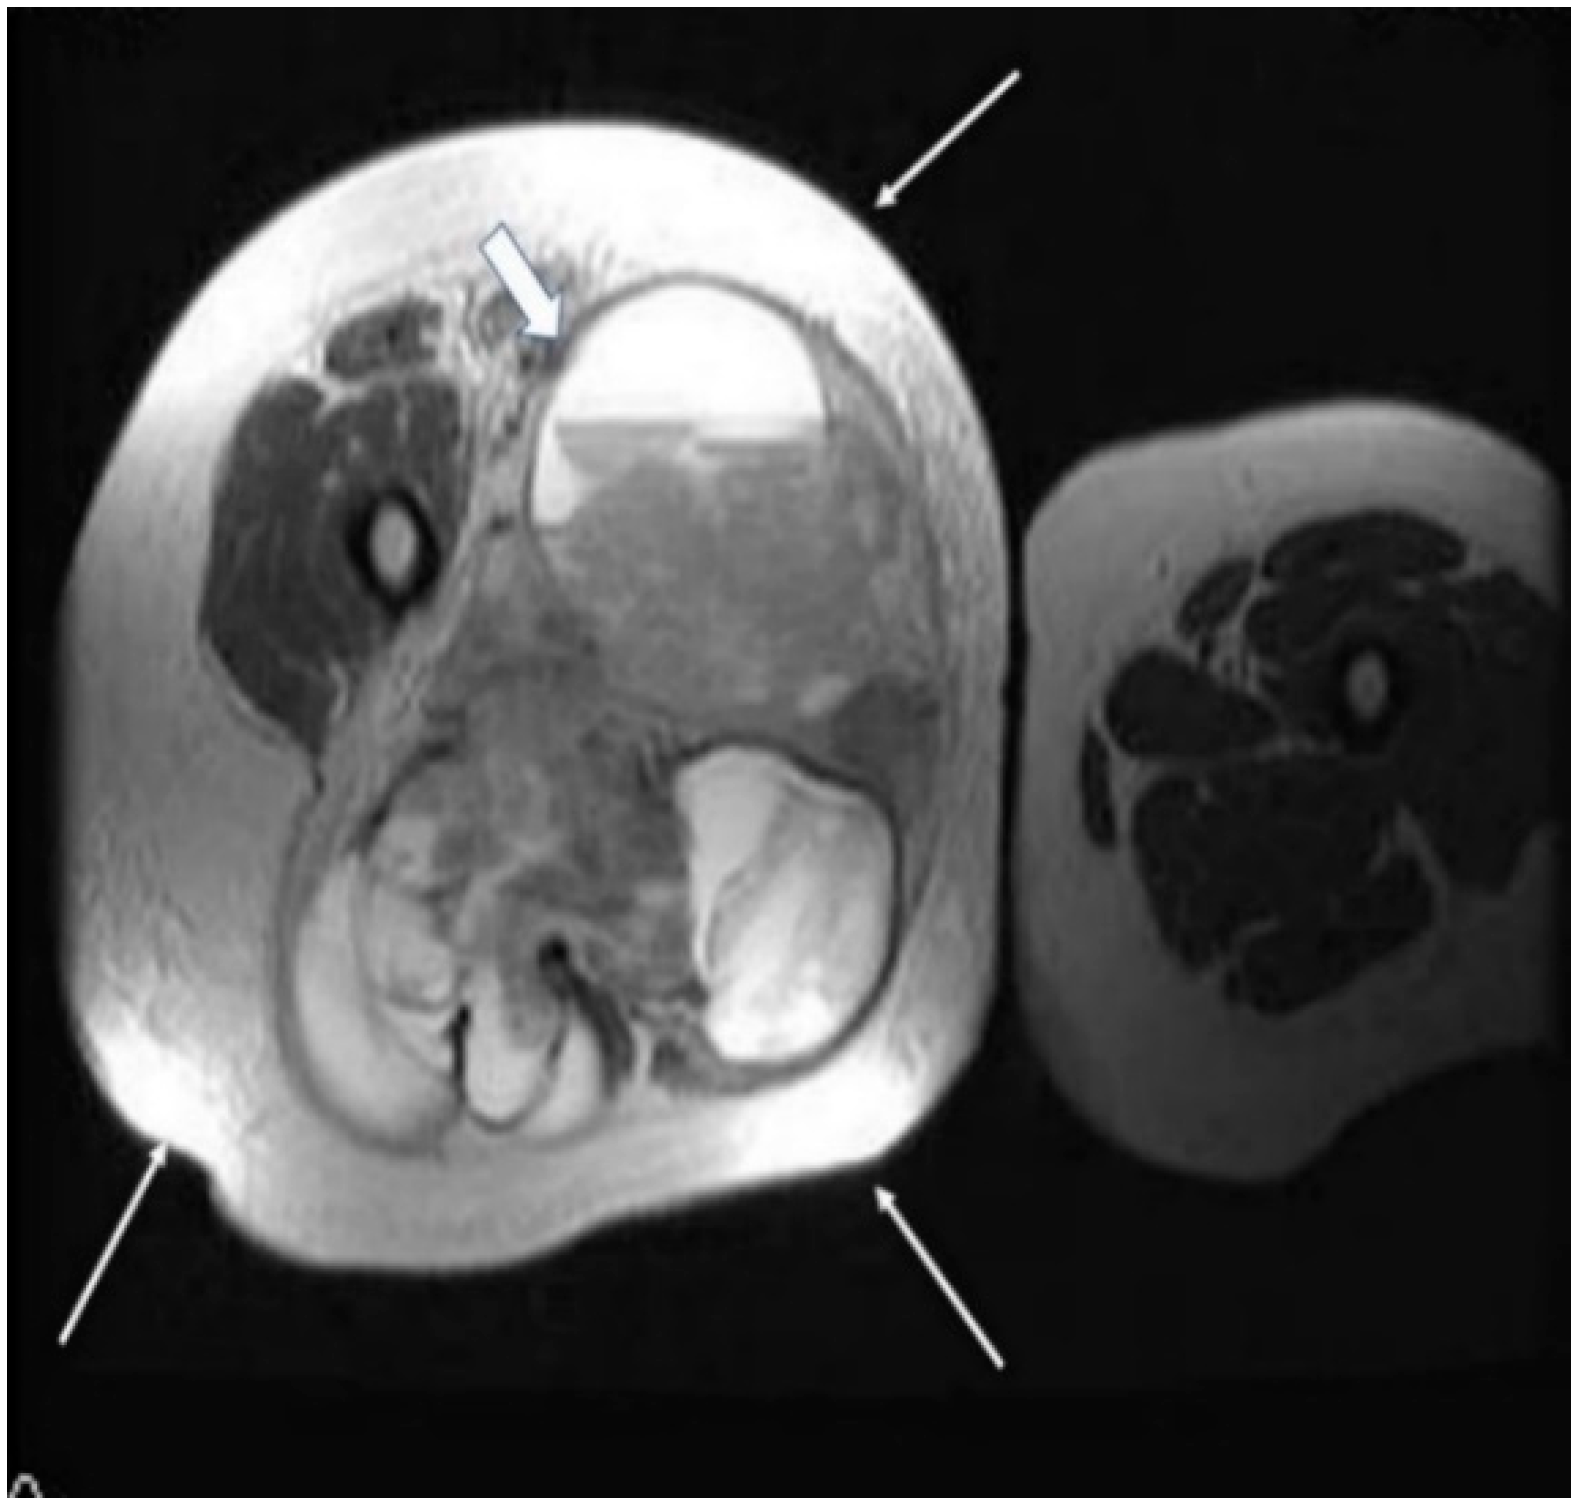

Magnetic resonance imaging (MRI) with contrast should be considered for tumors exceeding 2–3 cm and is probably the imaging method of choice for synovial sarcomas. MRI will provide valuable information regarding the extent of the tumor and the relationship with the surrounding anatomical structures; the use of a gadolinium contrast will enhance the amount of information that can be obtained since it is able to differentiate between hemorrhagic areas and solid tumoral tissue.

The T2 sequences are more specific for the diagnosis of soft tissue sarcomas and can reveal an inhomogeneous tumor, mainly with a hyperintense signal, in contrast with muscles, and the specific “triple sign” is present, representing a mixture of solid parts (medium hemorrhage and/or necrosis (high signal intensity) and calcifications or/and fibrotic areas (low signal intensity). The heterogeneity is completed by the presence of cystic parts with an aspect of fluid–fluid levels due to blood sedimentation (Figure 2 and Figure 3).

Figure 2.

A 40-year old female patient with synovial sarcoma. Image represents an axial MRI of the proximal right thigh—axial T2 FSE (fast spin echo) and FATSAT (fat saturation). There is an increased diameter of the right thigh because of a soft tissue mass (thin arrows), where an inhomogeneous mixture of solid and cystic areas is shown (block arrow).